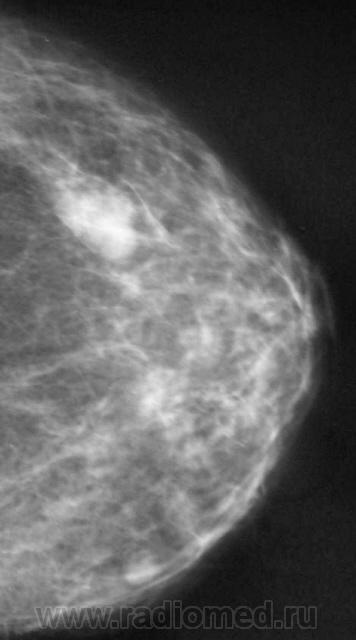

Ещё одна интересная маммография

Жалоб пациентка не предъявляет, просто иногда ощущает дискомфорт в мол.железах.

Кистозный ФАМ с одной стороны просто ФАМ с другой (где право-лево не указано на снимках)

Где прямые, где косые? Вероятно кисты, но могут быть и фиброаденомы, надо УЗИ и при кистах - пункционное удаление содержимого, при фиброаденомах - секторальная резекция.

А, мне, что-то больше симпатично, как "фиброаденомы".

Гадать кисты это или фиброаденомы без УЗИ - дело не благодарное, почему кисты ставлю на первое место потому, что чаще кисты бывают множественными.